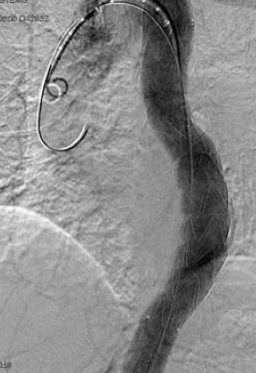

9. ábra.

A 7. képen látható eset angiogramja.